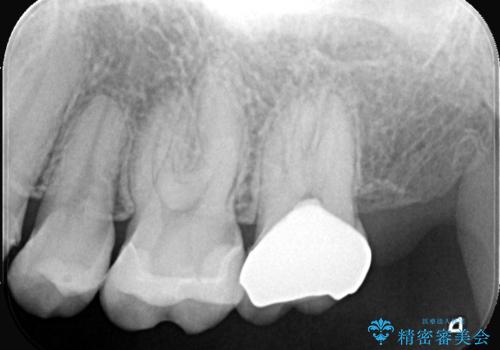

- 虫歯の治療を希望されました。一番奥の歯は虫歯が深かったことから神経を部分的に残す治療法(生活歯髄療法)や神経の治療(根管治療)についても説明し、治療介入をしました。

材料の特性を説明し、材質はどちらもセラミック、手前の歯は部分的な詰め物、奥の歯は被せ物での修復となりました。

左上7番は治療前の神経の検査では正常の範囲内の値を示しました。虫歯を削っていったところ神経まで到達したため、神経を部分的に残す治療法を選択しました。その後痛み等症状が出ず、また、神経の反応も正常であったため、被せ物にしています。